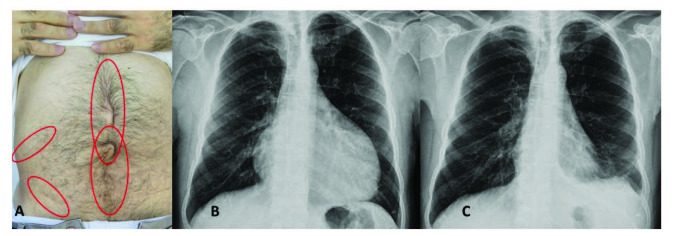

腹膜發(fā)作開始局限并迅速蔓延至整個腹部。腹膜炎癥會導(dǎo)致典型的腸梗阻癥狀,患者會遭受嚴(yán)重的胃痛。體格檢查顯示腹部肌肉僵硬、反跳痛和腸鳴音消失——臨床上這種緊急情況與急腹癥的手術(shù)原因無法區(qū)分。因此,隱匿性腹部手術(shù)史在良性陣發(fā)性腹膜炎患者中很常見(圖 1A)。在疑似病例中,影像學(xué)檢查可能有助于排除手術(shù)病理。腹部發(fā)作后可能會出現(xiàn)輕度反彈性腹瀉。盡管有戲劇性的表現(xiàn),但腹膜炎的所有體征和癥狀在 24-72 小時內(nèi)有效消退,沒有后遺癥,盡管慢性腹水和腹膜粘連的報道很少。

包含圖片、插圖等的外部文件。對象名稱為 turkjmedsci-50-1591-fig001.jpg

圖1:(A) 一位因多次腹部手術(shù)而留下疤痕的患者,(B) 胸部 X 光片顯示大量心包積液,(C) 同一患者用阿那白滯素治療后的胸部 X 光片。

心包炎是一種罕見病癥,見于 1%–2% 的患者。心包炎會出現(xiàn)胸骨后胸痛和呼吸困難等癥狀。心包填塞可能很少發(fā)生。心電圖顯示 ST 段抬高,胸部 X 光片可能顯示心臟輪廓的短暫擴大(圖 1B 和 1C),超聲心動圖顯示心包積液。在極少數(shù)情況下,反復(fù)性心包炎可能是良性陣發(fā)性腹膜炎的少有表現(xiàn),這可能與特發(fā)性心包炎相混淆 。